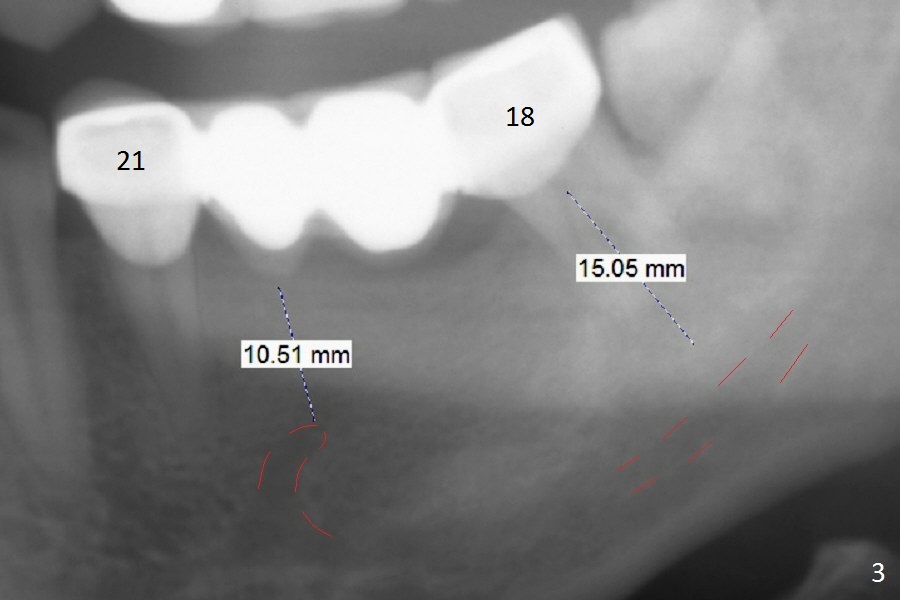

A 39-year-old woman has mobile FPDs at #2-6 (Fig.1,2) and 18-21 (Fig.3,4). Panoramic X-ray (Fig.1,3) was taken 10 years ago, while PAs (Fig.2,4) were taken lately. The abutment at #6 appears to be fractured (Fig.2 >), while that at #18 has 2nd caries (Fig.4 *). Removal of the FPDs determines salvageability of the abutments. The one at #6 may need RCT, B-U and crown or extraction/implant. In any event, implants will be placed at #3, 4, 18 and 20. To avoid the Inferior Alveolar Canal and Mental Loop, the implants will be as lingual as possible (Fig.3,4). For surgical and restorative stents, take Alginate impression as soon as the patient arrives.